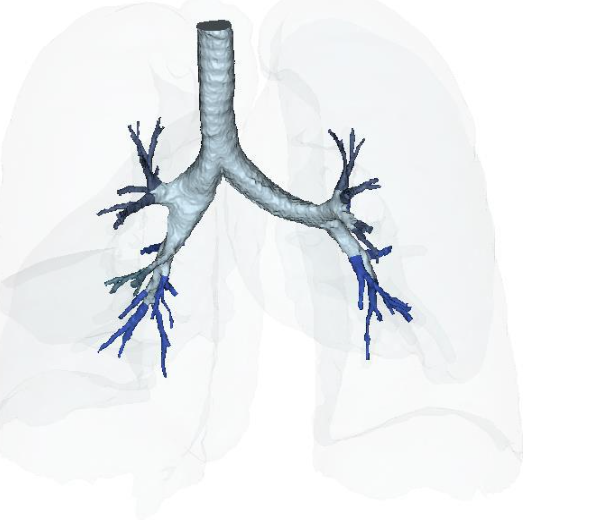

Figure 15A: Vascular Perfusion Changes Pre-treatment of Long COVID-19 lung vascular changes. Figure 15B: Post IV deployment cSVF therapy in Long COVID-19 clinical trial NCT04326036 at 6 months. Figure 16A: Restoration of the near terminal Tracheobronchial tree, pre-treatment showing blunting and loss of distal bronchioles. Figure 16B: Post-treatment IV cSVF with elongation of distal bronchiolar tree at six months. NOTE: With this post-treatment changes with cSVF was an accompanying reduction in airway resistance and pressures within the lung parenchyma. Higher pressures in pre-treatment image were located in the Upper lobes (less efficient and higher pressures in pre-treatment), whereas the shift from upper to lower lung parenchyma accompanied improve vascular supply and perfusion, and patients no longer experienced difficulties in inhalation capabilities.